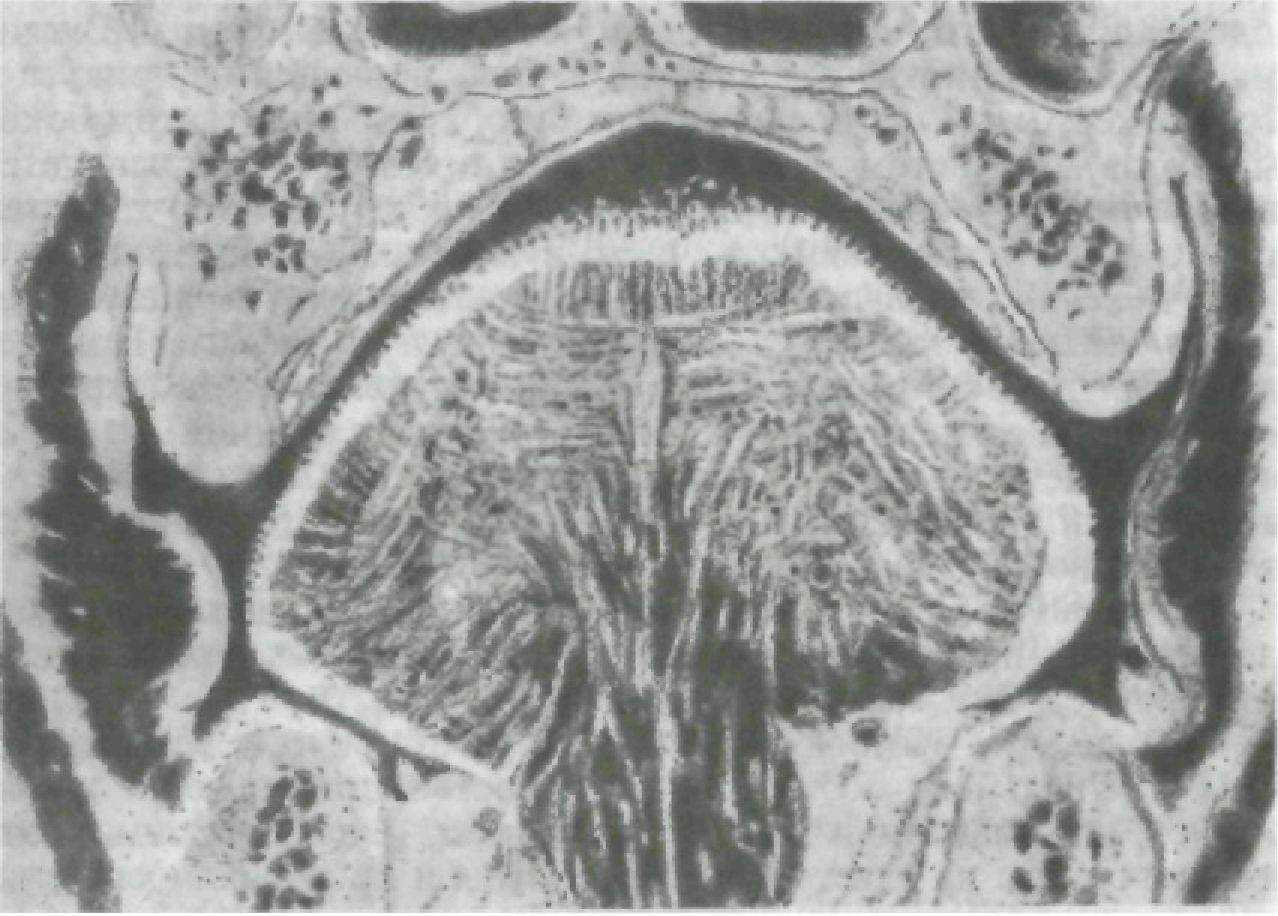

Посмотрев на разрез челюстно-лицевой области по фронтальной плоскости в области первых моляров (рис. 223), нужно обратить внимание на пространства в полости рта, где располагаются обычно зубные протезы. Альвеолярные отростки верхней и

Рис. 223. Разрез челюстно-лицевой области во фронтальной плоскости.

нижней челюстей на разрезе V-образные и обращены друг к другу острыми краями.

Слизистая оболочка щек и языка в значительной мере повторяет конфигурацию скатов альвеолярных отростков, но судя по рисунку неплотно прилегает к ним. В области свода преддверия, а также дна полости рта между альвеолярными отростками и слизистой оболочкой щек и языка имеется щелевидное пространство. Язык выходит на вершины альвеолярных отростков и почти соприкасается со слизистой оболочкой щек.

Язык является мощным мышечным органом, принимающим активное участие в акте жевания, глотания и образования речи. Поэтому конструирование искусственных зубных рядов и базисов протезов необходимо проводить в соответствии с функциональными особенностями движений и формой последнего. Зубная дуга ни в коем случае не должна быть зауженной, а базис нижнего протеза необходимо смоделировать таким образом, чтобы он имел вогнутую поверхность как с язычной, так и со щечной стороны (рис. 224).